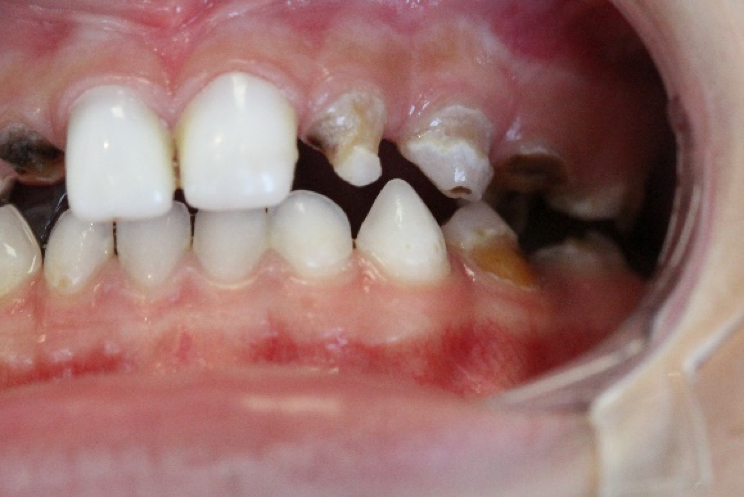

Paciente do sexo masculino, 7 anos de idade, compareceu ao consultório acompanhado pela mãe que se queixava de muitas lesões de cárie nos dentes de seu filho. Após anamnese, exame clínico observou-se presença de lesões de mancha branca nos elementos 72 e 73. (foto 1 e 2)